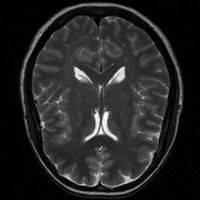

4.4 Qualitative Evaluation

In Figure 5 we analyze the prediction quality of our and compared approaches in a qualitative way. Considering modality propagation in MRI, we see that usage of uncertainty-aware patch invariance (UAPI) gives a better detailed weighting of the cerebrospinal fluid in the middle of the brain. In general, employing patch invariance yields better preservation of fine structures. This observation also applies to accelerated MRI enhancement. In particular, CUT and UAPI provide comparatively sharper knee images with more high-frequency details than the other methods.